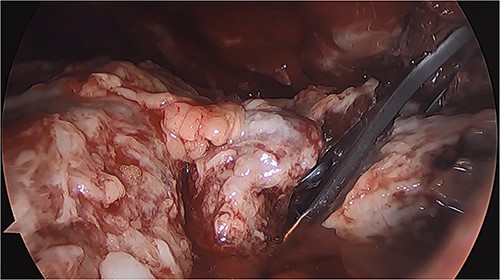

VATS was performed on 20 January 2021 for thoracic cavity lavage and placement of pleural drains (Fig. 6), along with abdominal laparoscopic revision and endoscopy for stent repositioning and nasojejunal tube placement. The patient showed clinical improvement after the procedure and with total parenteral nutrition support, enteral diet through the nasojejunal tube, broad-spectrum antibiotics guided by culture, and blood component transfusion.

Thoracoscopy (VATS) revealing the presence of fibrinopurulent tissue in the left thoracic cavity.